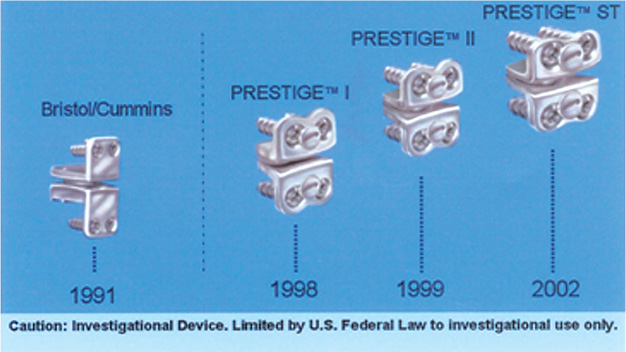

8 The Prestige family of disks traces its lineage back to the Cummins (Bristol) Artificial Cervical Joint (Fig. 8–1). The late Brian Cummins, senior consultant in neurosurgery at Frenchay Hospital in Bristol, U.K., became concerned about the need for repeated surgical therapy in patients with degenerative spinal disk disease undergoing anterior cervical fusion, particularly after two or more previous surgically or congenitally acquired fusions. Prof. Cummins recognized the potential clinical benefit of an artificial cervical joint and in 1989 began consultation with Colin Walker, head of the Department of Medical Engineering at Frenchay Hospital (DMEFH). Several concepts were considered; however, they ultimately elected to place a prosthetic joint in the intervertebral space after a standard anterior diskectomy. Several prototypes were manufactured in the DMEFH and in early 1991 the initial design was produced for clinical trial. The prosthetic joints were individually produced in the medical engineering shop and were made of Type 316 stainless steel (composition D: BS7262: part 1:1990 and ISO5832-1:1987). The prosthesis was basically a ball and socket joint that allowed flexion-extension, axial rotation, lateral bending, and, by making the ball slightly smaller than the saucer, slight translation. Fixation was initially achieved with a single anterior bone screw through each anterior flange. After the joint was placed in the first five patients, an additional screw site was added to the anterior flange of the joint and the screw sites were adjusted to ensure a more stable interface. The first five joints had simple stainless steel fracture screws. Subsequently, A-O locking screws were used to affix the joint anteriorly to the vertebral body. However, these screws were made of titanium, which added a variant metal to the process. Between February 1991 and August 1996, 22 joints were placed in 20 patients. All patients provided detailed informed consent before undergoing this innovative surgical procedure. Nineteen of the 20 cases were associated with previous surgical or congenital fusions at single and multiple levels of the cervical spine. Patients were operated because of symptomatic adjacent segment cervical stenosis, spondylosis, or herniated disk with associated myelopathy, radiculopathy, or, in one case, intractable pain. The joint appeared to be stable, it preserved motion, and it was both biomechanically and biochemically compatible. Subsidence was not observed despite several incidences of fixation screw fracture. After review in July 1996 of the medical records, examination of the patients, and obtaining delayed cervical spine motion x-rays, the results revealed this prosthesis to be suitable for cervical disk replacement.1 Figure 8–1 Metal/metal cervical disk clinical history.